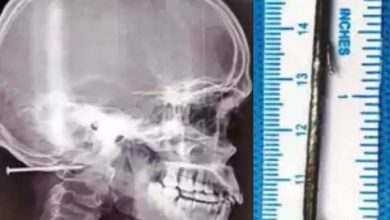

തലയില്‍ തുളഞ്ഞ് കയറിയത് 2 ഇഞ്ച് നീളമുള്ള ആണി; 6 മണിക്കൂര്‍ നീണ്ട ശസ്ത്രക്രിയക്കൊടുവില്‍ നീക്കംചെയ്തു

ചെന്നൈ: ആറുമണിക്കൂര്‍ നീണ്ട ശസ്ത്രക്രിയക്കൊടുവില്‍ 23 വയസുകാരന്റെ തലയില്‍ നിന്ന് 2 ഇഞ്ച് നീളമുള്ള ആണി നീക്കം ചെയ്ത് ഡോക്ടര്‍മാര്‍. ചെന്നൈയിലെ സ്വകാര്യ ആശുപത്രിയില്‍ കഴിഞ്ഞദിവസമാണ് സംഭവം. ജോലിക്കിടെ സഹപ്രവര്‍ത്തകന്റെ നെയില്‍ ഗണ്ണില്‍ നിന്ന് തെറിച്ച ആണിയാണ് ഉത്തര്‍പ്രദേശ് സ്വദേശിയായ ബ്രഹ്‌മ എന്ന യുവാവിന്റെ തലയില്‍ തുളഞ്ഞ് കയറിയത്. മരണം വരെ സംഭവിക്കാവുന്ന അപകടമായിരുന്നു യുവാവിന് സംഭവിച്ചത്. എന്നാല്‍, ഓപ്പറേഷന്‍ കഴിഞ്ഞ് രണ്ടാം ദിവസം യാതൊരു ആരോഗ്യപ്രശ്‌നവും ഇല്ലാതെ യുവാവിനെ ഡിസ്ചാര്‍ജ് ചെയ്തു. നവലൂരിലെ പാക്കേജിങ് ഫാക്ടറിയിലാണ് ബ്രഹ്‌മ ജോലി ചെയ്യുന്നത്. ജൂലൈ 4ന് ഇവിടെ നിലം തുടയ്ക്കുന്നതിനിടെയാണ് സഹപ്രവര്‍ത്തകന്റെ നെയില്‍ ഗണ്ണില്‍ നിന്നുള്ള ആണി തലയില്‍ തറച്ചുകയറിയത്. പെട്ടെന്ന് തലയുടെ പിന്നില്‍ ശക്തമായ വേദന തോന്നുകയായിരുന്നെന്നാണ് അപകടത്തെക്കുറിച്ച് യുവാവ് പറയുന്നത്. രക്തം കണ്ട സഹപ്രവര്‍ത്തകര്‍ ഓടിയെത്തി പരിശോധിച്ചപ്പോഴാണ് രണ്ട് ഇഞ്ച് നീളമുള്ള ആണ് തലയില്‍ തറഞ്ഞ് കയറിയെന്ന് മനസിലായത്. തലയും കഴുത്തും കൂടിച്ചേരുന്ന സ്ഥലത്താണ് ആണി തുളഞ്ഞ് കയറിയതെന്ന് മനസിലാക്കിയ…